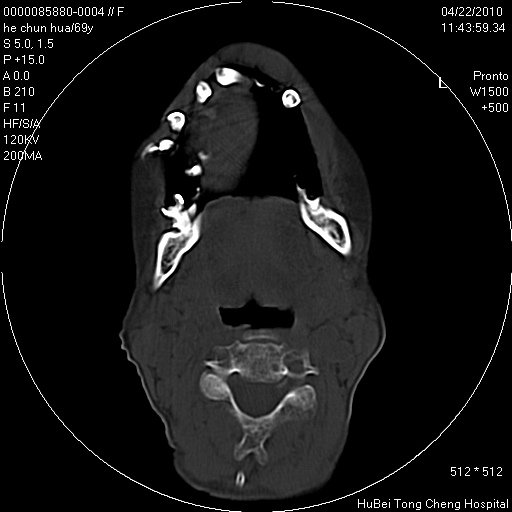

标题: CT25937:女,69Y

硬腭部包块十余年,渐进性增大。

病程长,考虑巨细胞修复性肉芽肿可能性大;

鉴别:神经源性病变、硬结病等。

五楼说得有道理,支持一下。巨细胞修复性肉芽肿好象是外伤出血后引起的修复性改变,骨质呈溶骨性破坏,但病程呈良性过程。

骨源性肿瘤 造秞细胞瘤

考虑硬腭部肿瘤恶变,gcrg可能,鉴别于gct。